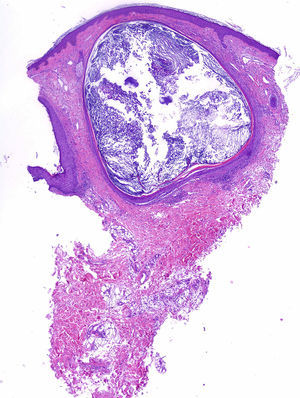

Presentamos el caso de un varón de 48 años de edad, con antecedentes de adenocarcinoma de pulmón con metástasis cerebrales, que recibió tratamiento paliativo con radioterapia holocraneal que incluye a los pabellones auriculares a dosis de 30Gy en 10 fracciones (2 campos laterales y opuestos conformados de fotones sobre el sistema nervioso central; la dosis total que reciben los pabellones auriculares se calcula que está entre 20-25Gy). Acudió por presentar lesiones en la cara posterior de ambos pabellones auriculares de 3 meses de evolución, asintomáticas. Había padecido alguna lesión similar aislada desde la juventud, pero habían aparecido múltiples lesiones un mes después de recibir radioterapia. A la exploración clínica se observaron múltiples pápulas blanquecinas milimétricas, de superficie brillante, agrupadas sobre una base eritematosa, bilaterales y localizadas en los pabellones auriculares (figs. 1 y 2). Se realizó una biopsia en sacabocados que evidenció un quiste folicular infundibular, con queratina ortoqueratósica en su interior (fig. 3). En función de los antecedentes personales y los hallazgos clínicos e histológicos se diagnosticó MEP posradioterapia.

En la histología se evidencian pequeños quistes en la dermis, que contienen queratina ortoqueratósica revestida por un epitelio escamoso con capa granulosa, acompañados de un leve infiltrado perivascular mixto o de linfocitos2,4.